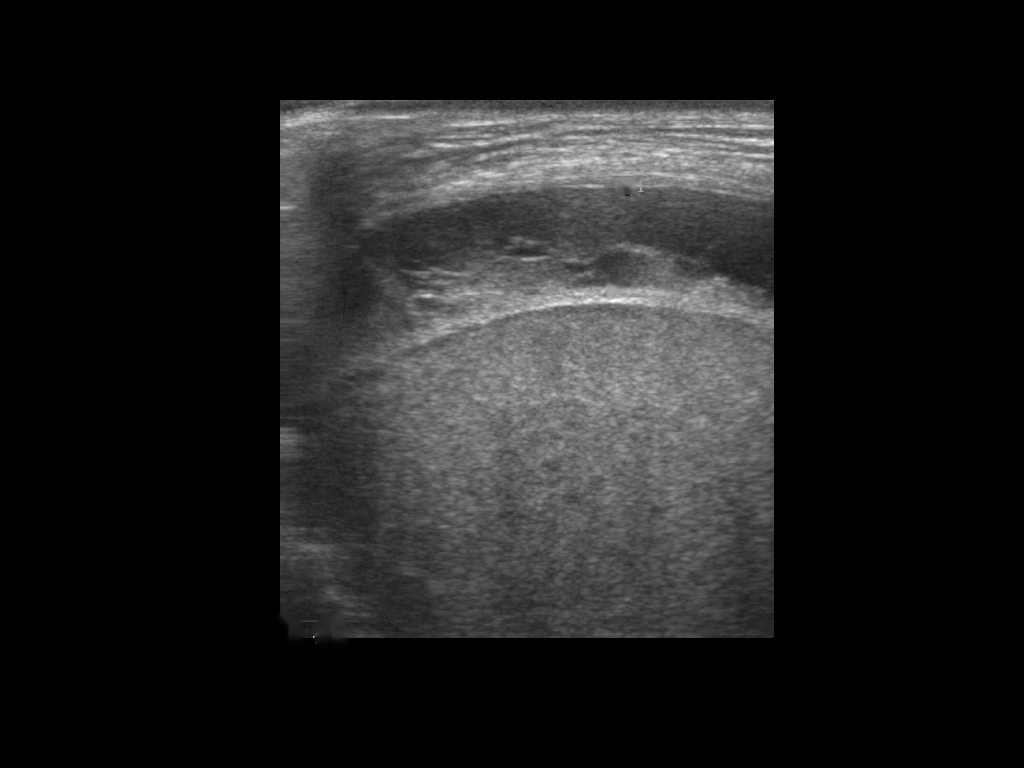

A total of 143 images were acquired from 59 patients. The images were obtained at the left and right PLAPS (PosteroLateral Alveolar and/or Pleural Syndrome) and subcostal views [4] with linear array and curved array (abdominal) ultrasound probes. The data were split according to the use of these probes into two datasets of 51 and 92 images, respectively for linear array and curved array. We denote these datasets as Dataset A (linear array) and Dataset B (curved array). All images were annotated at the time of acquisition to measure the extent of the effusion. These annotations consisted of small crosses at the top and bottom of the deepest area of effusion. See Figure 1 (left column) for example images.

Before being used for training and evaluating the models, each image was automatically cropped using a rectangular/cone mask to remove non-imaging content. Next, we applied an inpainting text algorithm using keras-ocr followed by template matching and edge detection algorithms from opencv to remove the annotations that were added to the images to measure the effusion. Examples of the outputs of this preprocessing are shown in Figure 1 (centre column).

All images in both datasets were manually segmented using the ITK-SNAP software [14] (www.itksnap.org) by a trained observer. Examples of ground truth segmentations are shown in Figure 1 (right column). These segmentations acted as ground truths for training and evaluating the proposed models. Additionally, a second trained observer performed independent segmentations of subsets of 10 random images each from the two datasets. These were used to compute an estimate of inter-observer variability in the manual segmentation process.